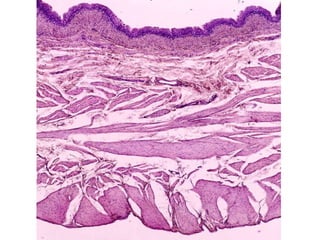

Vías urinarias La orina fluye secuencialmente hacia un  cáliz menor,  un  cáliz mayor  y la  pelvis renal  y abandona cada riñón a través del  uréter  que la conduce hasta la  vejiga , donde se almacena. Al final la orina se elimi­na a través de la  uretra . Todos estos conductos de excreción de la orina (vías urinarias), excepto la uretra, tienen la misma organización general; una mucosa (revestida por epitelio de transición o urotelio), una muscular y una adventicia (o, en algunas regiones, una serosa).

Epitelio de transición ,  polimorfo  o  urotelio El urotelio se podrá encontrar en dos estados, uno se denomina  estado contraído  y el otro  relajado . En el estado contraído (vejiga vacía) hay  muchas ca-pas celulares , las células apicales se  hacen globosas . Cuando el epitelio se estira al llenase la vejiga (estado relajado) se llegan a distinguir  sólo dos capas  de células.

Todas las células de este epitelio presentan finas prolongaciones mediante las cuales están ancladas a la membrana basal. A estas células se las denomina  células en forma de raqueta  y el glucógeno almacenado perinuclear es utilizado para poder obtener energía y lograr este reordenamiento a medida que cambia el volumen vesical.

Uréteres La superficie luminal de la pared del uréter está revestida por un epitelio de transición (urotelio). El resto de la pared está compuesto por músculo liso y tejido conectivo. El músculo liso está organizado en tres capas: una  longitudinal interna , una  circular media  y una  longitudinal externa .

Vejiga En los  cortes histológicos  de rutina obtenidos de la vejiga vacía las células epiteliales superficiales suelen ser cuboides y protruir dentro de la luz. Con frecuencia se describen como abombadas o "en cúpula" por la curvatura de su superficie apical, las células apicales son globosas y esta es una diferencia muy importante para no confundir al urotelio de la vejiga con el epitelio plano estratificado de la piel.

Vías urinarias Laorina fluye secuencialmente hacia un cáliz menor, un cáliz mayor y la pelvis renal y abandona cada riñón a través del uréter que la conduce hasta la vejiga , donde se almacena. Al final la orina se elimi­na a través de la uretra . Todos estos conductos de excreción de la orina (vías urinarias), excepto la uretra, tienen la misma organización general; una mucosa (revestida por epitelio de transición o urotelio), una muscular y una adventicia (o, en algunas regiones, una serosa).

Epitelio de transición, polimorfo o urotelio El urotelio se podrá encontrar en dos estados, uno se denomina estado contraído y el otro relajado . En el estado contraído (vejiga vacía) hay muchas ca-pas celulares , las células apicales se hacen globosas . Cuando el epitelio se estira al llenase la vejiga (estado relajado) se llegan a distinguir sólo dos capas de células.

Todas las célulasde este epitelio presentan finas prolongaciones mediante las cuales están ancladas a la membrana basal. A estas células se las denomina células en forma de raqueta y el glucógeno almacenado perinuclear es utilizado para poder obtener energía y lograr este reordenamiento a medida que cambia el volumen vesical.

Uréteres La superficieluminal de la pared del uréter está revestida por un epitelio de transición (urotelio). El resto de la pared está compuesto por músculo liso y tejido conectivo. El músculo liso está organizado en tres capas: una longitudinal interna , una circular media y una longitudinal externa .